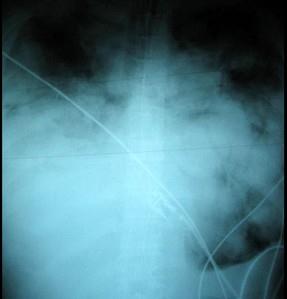

问题 33岁,男,咳嗽1周,有骨肉瘤病史,请结合胸片和CT选出最可能的诊断 ( )

选项 A、结节病 B、错构瘤 C、粟粒性肺结核 D、骨肉瘤转移 E、肺梗死

答案 D